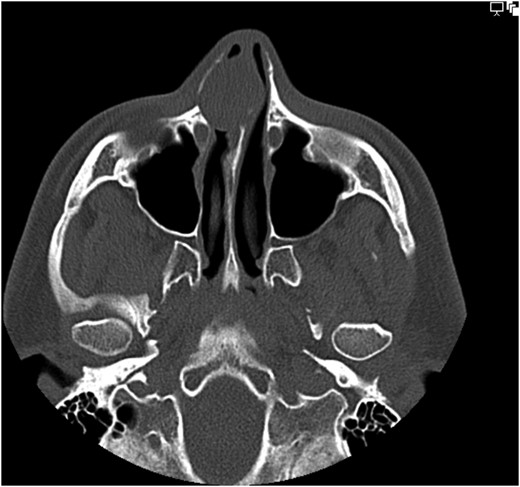

Non-contrast CT assessment of the sinonasal region was performed which revealed a soft tissue lesion arising from the right side of the nasal septum (Fig. 1). At the initial discussion at the local head and neck multidisciplinary team meeting, radiological opinion was that the lesion may possibly represent olfactory neuroblastoma, inverted papilloma or pleomorphic adenoma of the septum and that MRI would be beneficial in diagnosis. MRI imaging of the lesion showed general increased T2 signal but with heterogeneous nodular T2 heterogeneity (Fig. 2a and b). On the unenhanced axial T1-weighted sequence a small focus of T1 shortening was noted in keeping with some low volume focal cystic degeneration within the tumour (Fig. 2c).